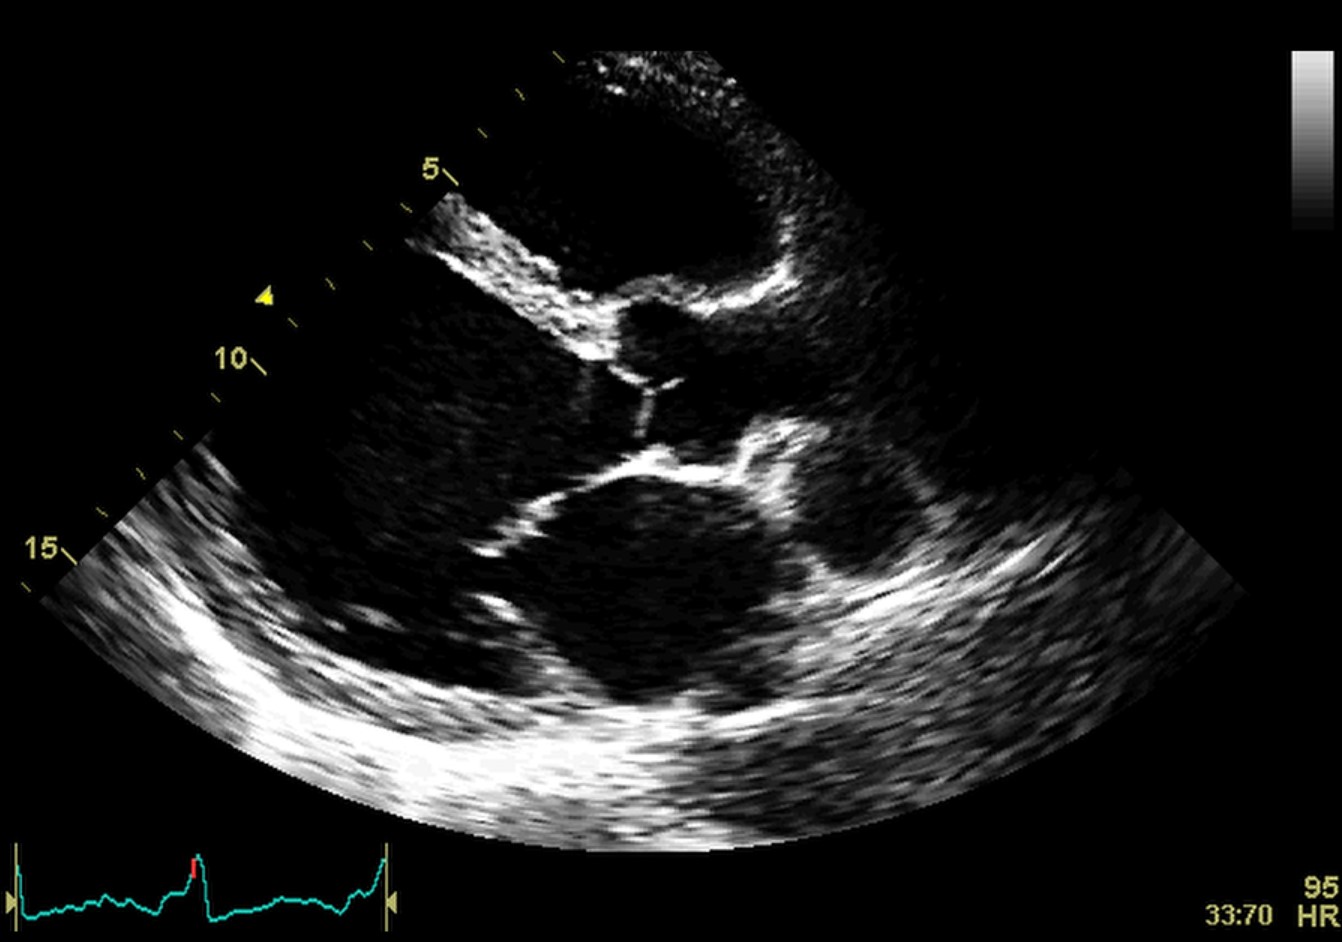

Arrhythmogenic cardiomyopathy (AC) is defined by fibrous and fibro-fatty replacement especially of the RV myocardium, affecting the inflow and outflow tract, but also the apex. This process most commonly affects the posterior and inferior areas of the right ventricular inflow tract adjacent to the tricuspid valve, but it also affects the anterior infundibulum and the apex, thus forming what is known as the “triangle of dysplasia”. According to recent data, there is also involvement of the postero-lateral wall of the LV. In the LV the fibro-fatty replacement determines a transmural lesion but the process starts from the subepicardial to the subendocardial LV layers. It has been demonstrated that in left ACM, the scar tissue tends to localize in the inferolateral subepicardial LV wall. In the initial assessment of AC, these typical regional wall motion abnormalities may be detected. Later changes may involve the RV free wall and become global, producing RV dilation (Fig. 11 and Appendix Video 6). Echocardiography is the first line and sometimes a sufficient method of evaluation in patients with AC.

Fig. 11.Echocardiographic aspect of AC. Apical 4 chamber view showing dilation and thick right ventricular free wall. A video of the apical 4 chamber view is available online (Appendix Video 6).